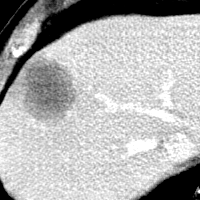

MRI

Refer to caption

Target\mathrm{Target}

Zoomed

StolenEPD{\mathrm{Stolen}}^{\mathrm{D}}_{\mathrm{EP}}

StolenEPD1{\mathrm{Stolen}}^{\mathrm{D1}}_{\mathrm{EP}}

StolenITD{\mathrm{Stolen}}^{\mathrm{D}}_{\mathrm{IT}}

StolenITD1{\mathrm{Stolen}}^{\mathrm{D1}}_{\mathrm{IT}}

Figure 7: Lossy image reconstructions on CT (row 1, 2) and MRI (row 3, 4) images, where the row 2, 4 provide a zoomed-in view of the bounding box region of the row 1, 3. The leftmost column represents the target images, while the subsequent four columns show the stolen images reconstructed by the decoder D or D1 in two scenarios.

A visual comparison between target and stolen images is available in Fig. 7. We observe that the stolen images from IT Scenario closely resemble the input ones, particularly in the tumor regions, whereas stolen images from EP Scenario exhibit blurring artifacts in finer details. In both cases, the stolen images reconstructed by D1D1 demonstrate a comparable quality to those reconstructed by DD, thus further confirming the effectiveness of the reduced decoder D1D1.